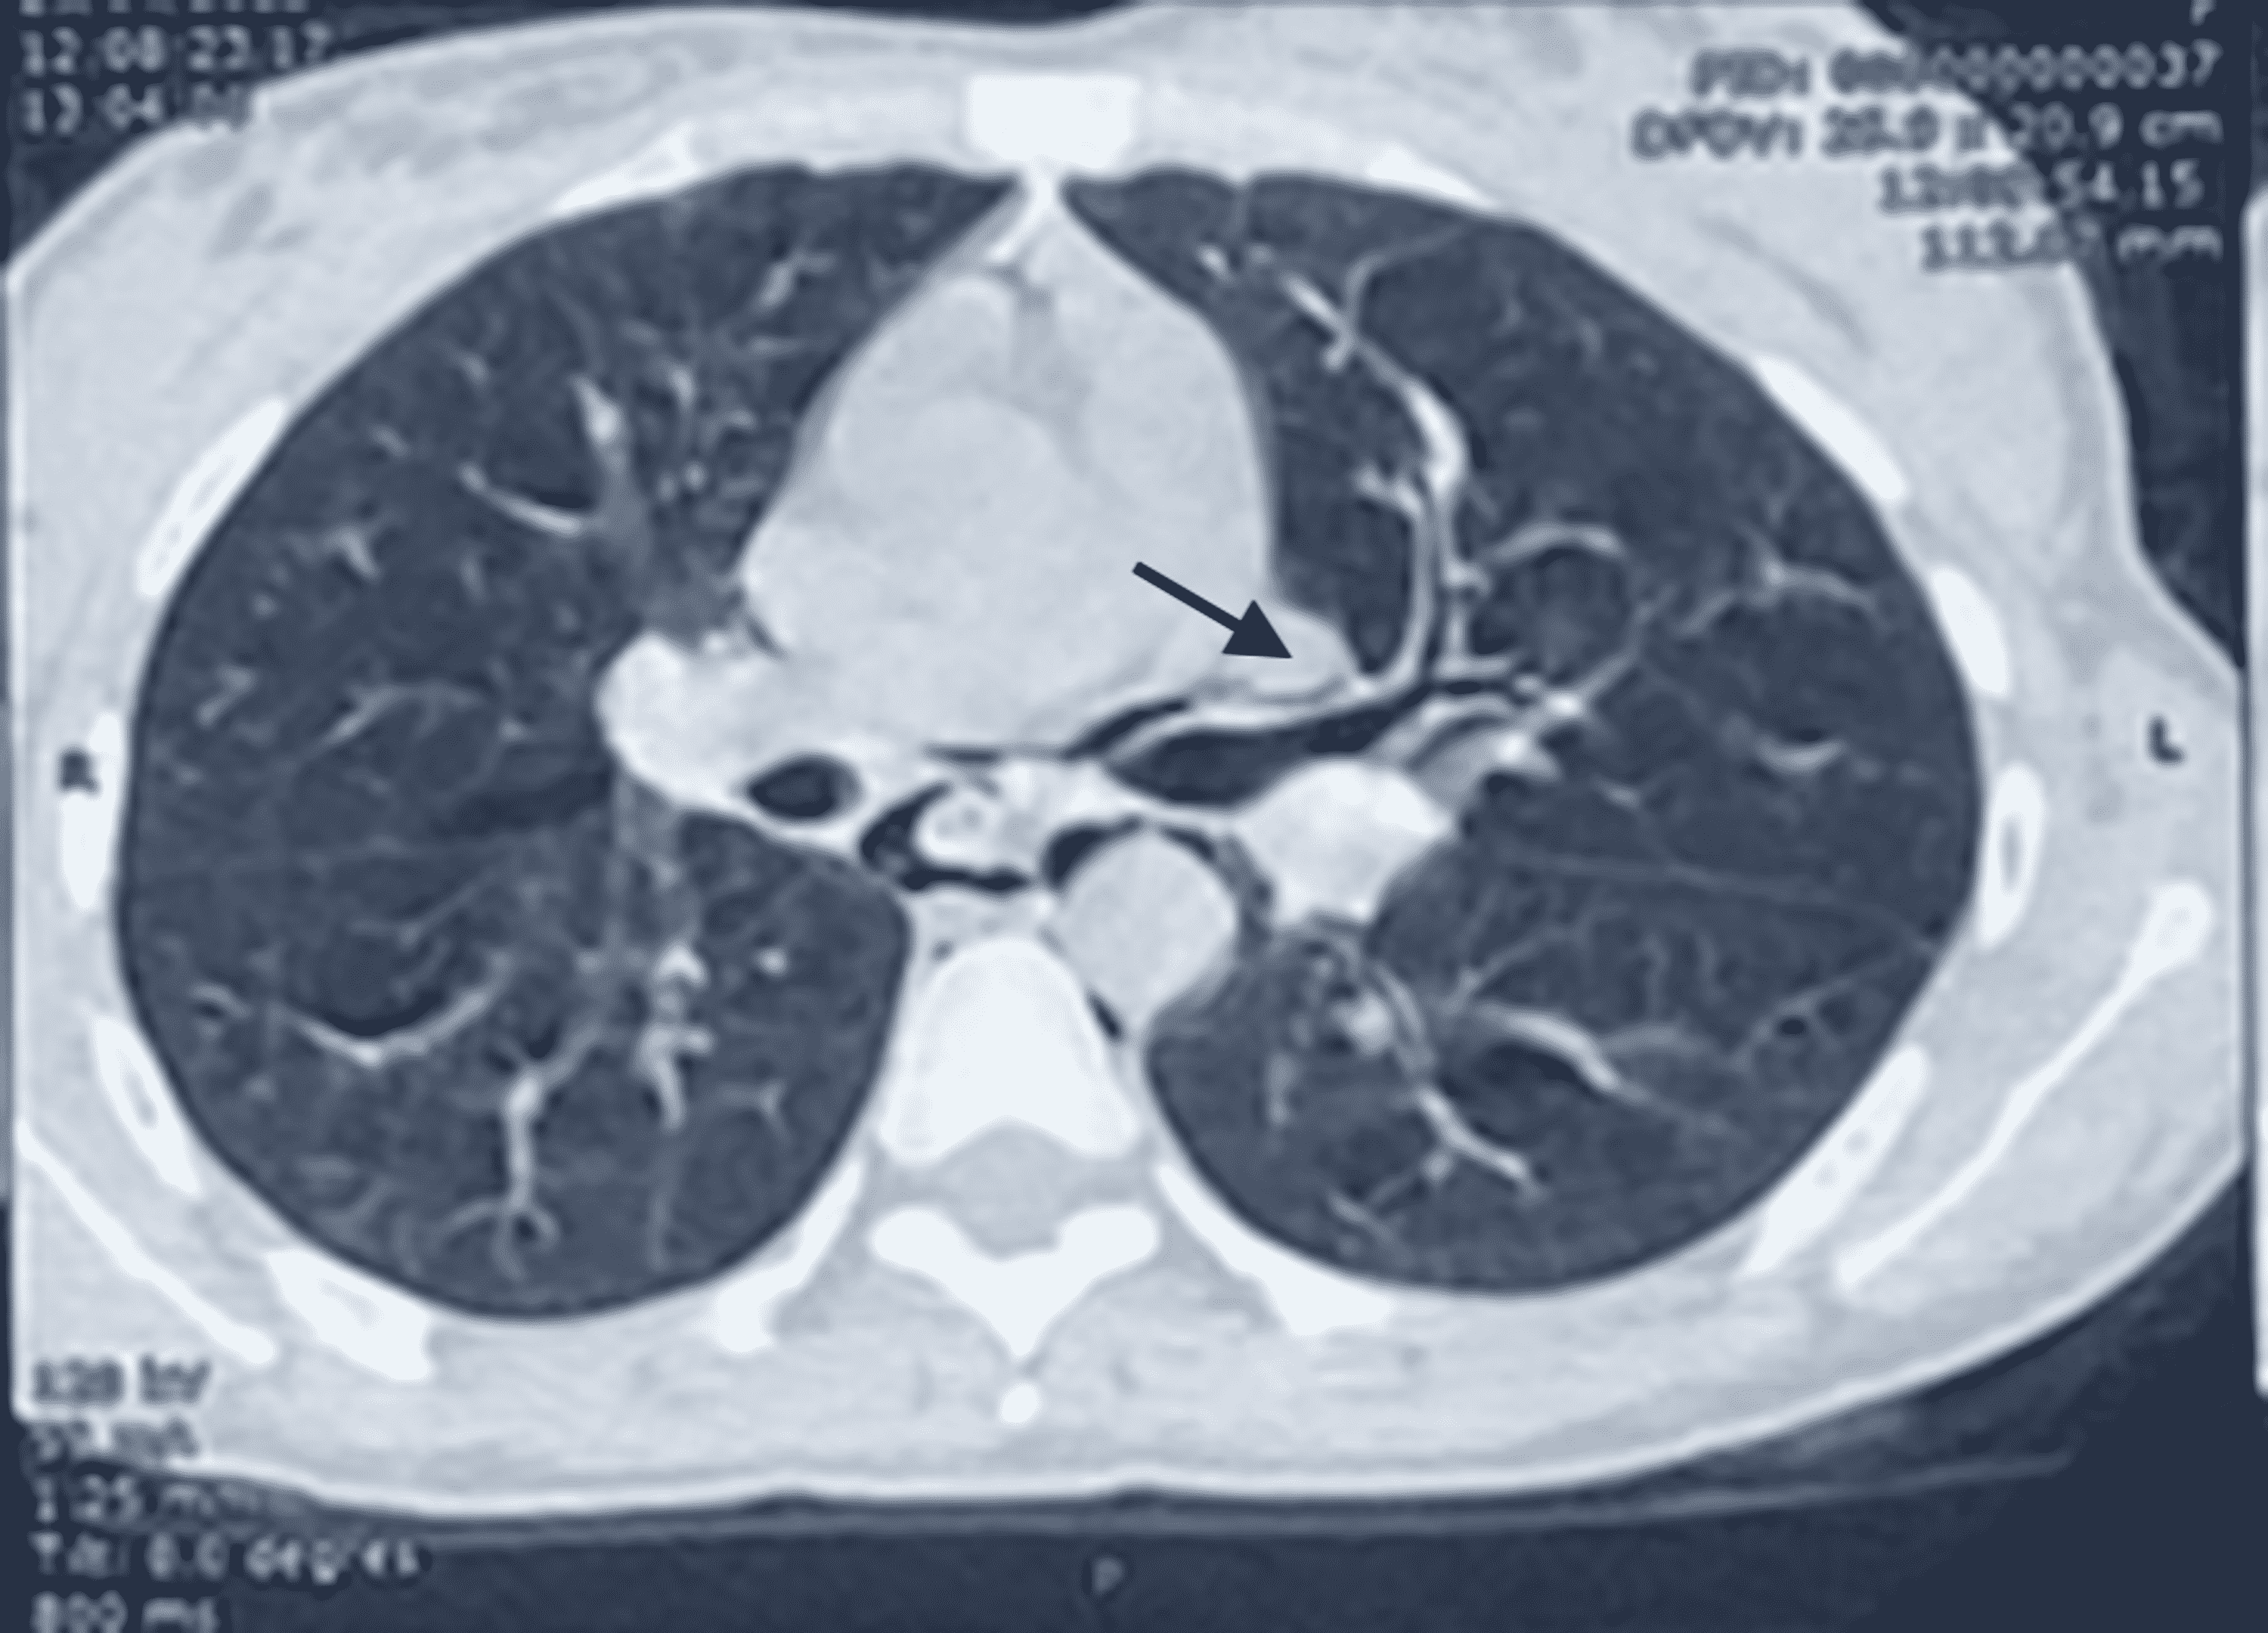

Macklin Effect . The macklin effect refers to pneumomediastinum caused by alveolar rupture and pulmonary interstitial emphysema tracking to the mediastinum along the peribronchovascular. Learn about the causes, clinical presentation, radiographic features and management of pneumomediastinum. Blunt traumatic alveolar ruptures, air dissection along bronchovascular. The macklin effect is a possible cause of pneumomediastinum in severe blunt chest trauma, involving air dissection along. The macklin effect is a rare but potentially serious complication of pneumomediastinum, caused by the. The macklin effect appears on thoracic computed tomography (ct) as linear collections of air contiguous to the. The aim of this review article is to describe the ct imaging spectrum of the.

The macklin effect appears on thoracic computed tomography (ct) as linear collections of air contiguous to the. Learn about the causes, clinical presentation, radiographic features and management of pneumomediastinum. The macklin effect is a rare but potentially serious complication of pneumomediastinum, caused by the. The macklin effect refers to pneumomediastinum caused by alveolar rupture and pulmonary interstitial emphysema tracking to the mediastinum along the peribronchovascular. Blunt traumatic alveolar ruptures, air dissection along bronchovascular. The macklin effect is a possible cause of pneumomediastinum in severe blunt chest trauma, involving air dissection along. The aim of this review article is to describe the ct imaging spectrum of the.

Macklin Effect The aim of this review article is to describe the ct imaging spectrum of the. Learn about the causes, clinical presentation, radiographic features and management of pneumomediastinum. The macklin effect refers to pneumomediastinum caused by alveolar rupture and pulmonary interstitial emphysema tracking to the mediastinum along the peribronchovascular. Blunt traumatic alveolar ruptures, air dissection along bronchovascular. The macklin effect is a possible cause of pneumomediastinum in severe blunt chest trauma, involving air dissection along. The macklin effect appears on thoracic computed tomography (ct) as linear collections of air contiguous to the. The aim of this review article is to describe the ct imaging spectrum of the. The macklin effect is a rare but potentially serious complication of pneumomediastinum, caused by the.